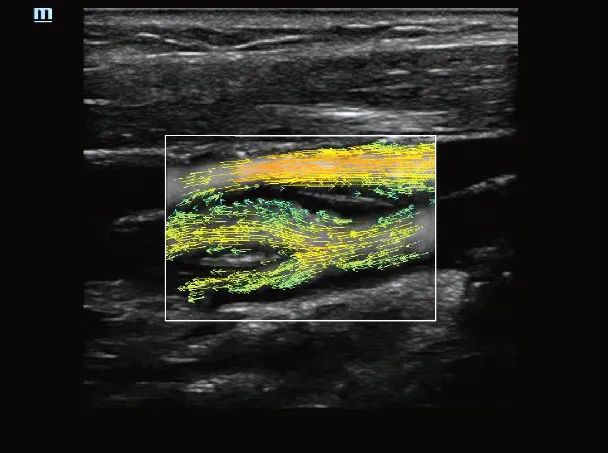

动态向量血流

动态向量血流V-Flow

通过彩色编码的向量箭头来追踪血流速度的大小和方向,生动且准确地显示外周血管的血流动力学特征,包括血管的管径、走行、分布和血管的丰富程度。依靠其高性能的彩色多普勒超声功能,能够显示直径在两毫米以下的细小血管,以及低速血流、低流量的血流,用于评价脏器血流灌注和病灶的血供特点,且无角度依赖,是极具价值的血流动力学研究工具。